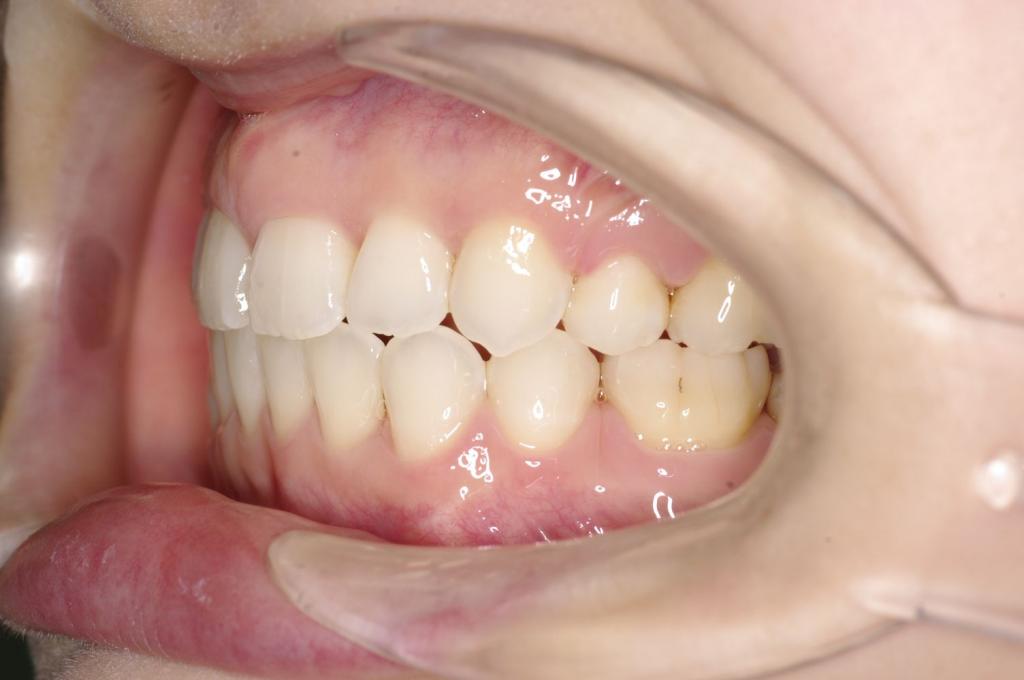

前歯、出っ歯・開咬の矯正治療

(治療期間、治療前後写真、治療方法、費用)WORKS